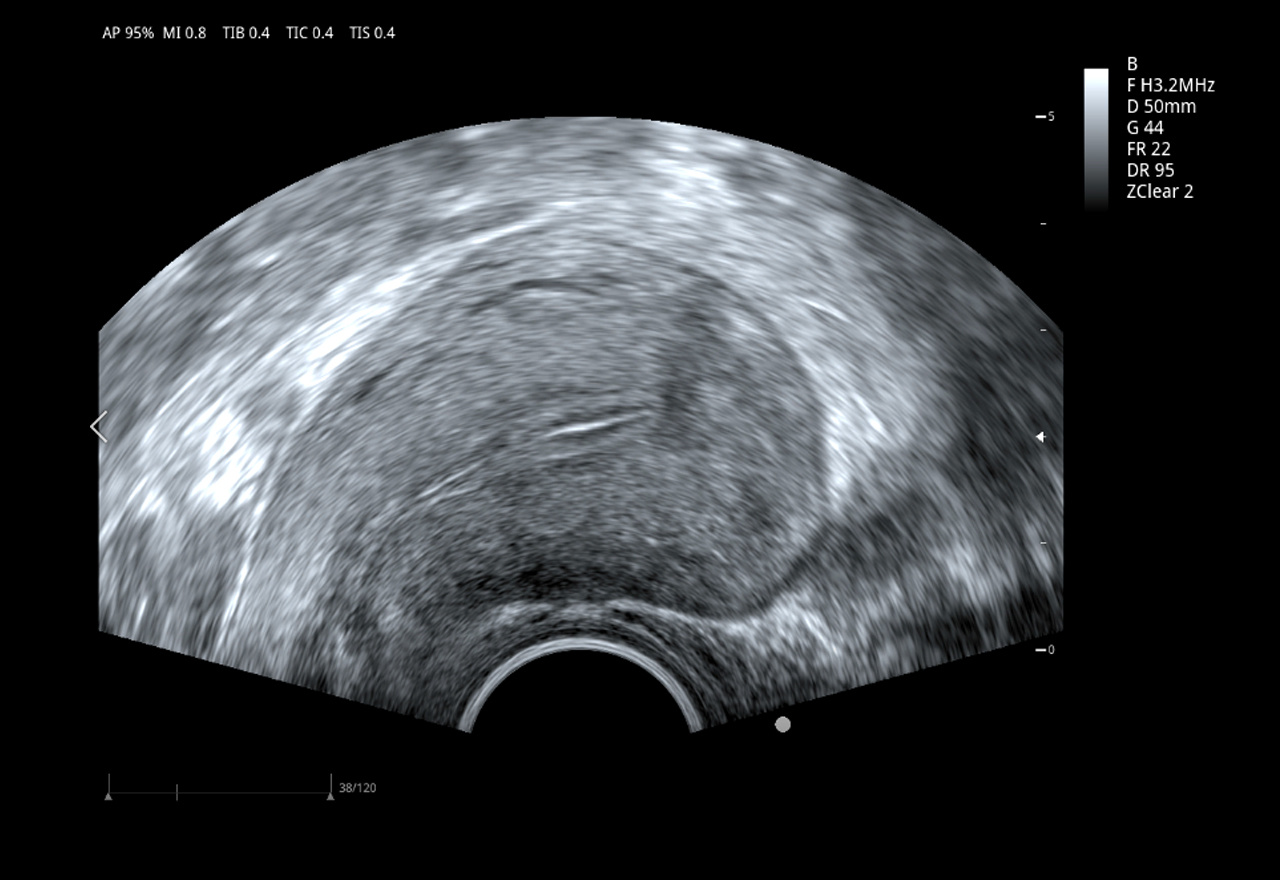

Imágenes clínicas extraordinarias

Imágenes con filtro espacial adaptativo – zonClear

ViV 20 está configurado con un algoritmo avanzado de filtro espacial adaptativo y se combina con una técnica de filtrado temporal con compensación de movimiento. Reduce eficazmente el ruido de speckle y mejora significativamente la visualización de los límites tisulares y la visualización del eco tisular mediante la detección de la ubicación de los límites anatómicos.